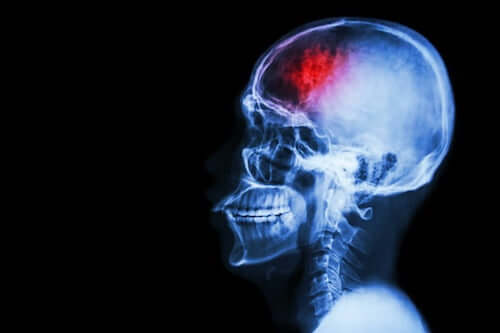

Udar to zaburzenie, które może pozostawić po sobie poważne konsekwencje oraz umiarkowany do ciężkiego stopień niepełnosprawności. Istnieją jednak inne rodzaje następstw, do których możemy przywiązywać mniejszą wagę, ale które są równie ważne. Są to zmiany emocjonalne i behawioralne, o których będziemy mówić w tym artykule.

Udar to nagłe zaburzenie krążenia krwi w mózgu, które powoduje połączenie objawów fizycznych i zaburzeń psychicznych, które mogą utrzymywać się z czasem. Dotyka 130 000 osób rocznie i szacuje się, że ponad 300 000 będzie miało ograniczenia funkcjonalne w wyniku udaru.